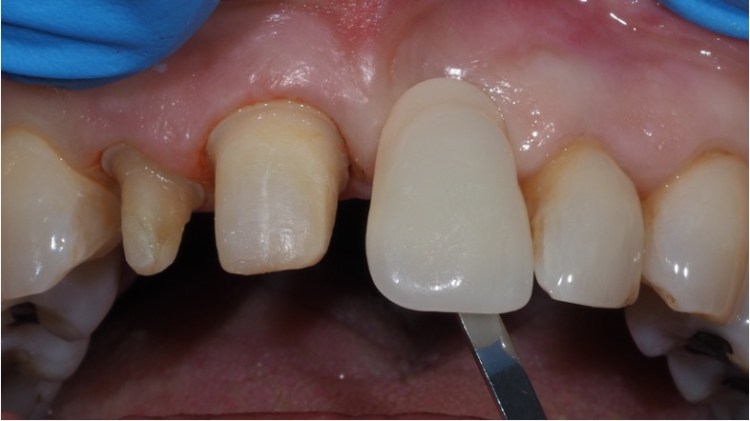

Conventional bridges involve preparing the underlying tooth structure. This is more destructive but can be a good choice if an adjacent tooth already has or will need a crown. In this case the single crown was replaced at the same time.